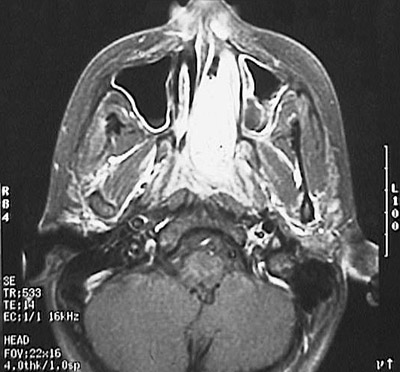

This CT scan of the head reveals a brightly enhancing angiofibroma filling and expanding the nasal cavity on the left.